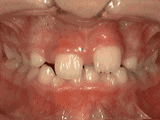

Openbite: Front teeth don't touch

openbite

Patient sucked her thumb as a young child. She started treatment at age thirteen. She had braces and a special appliance — called a crib — to retrain the tongue, for twenty-eight months. Now she can bite the lettuce out of a sandwich.